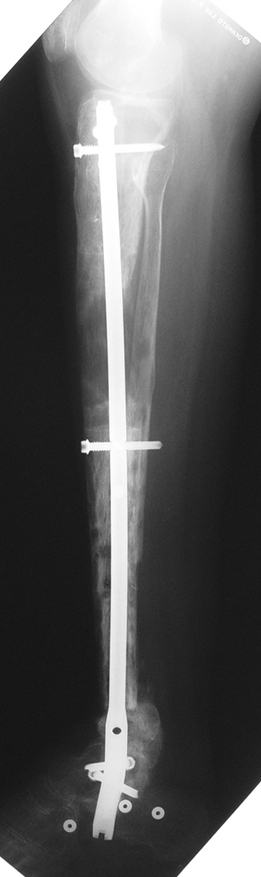

Case 1